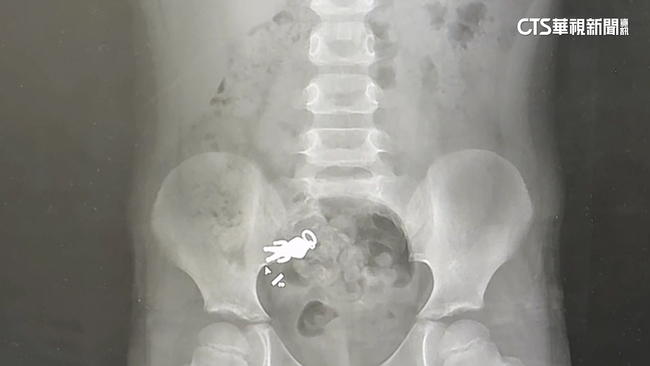

在社群平台上引發網友熱烈討論的,宜蘭男童與「超人力霸王」的「合體X光照」,昨(9)日晚終於有了最新的進展。

歷經了漫長的等待,這一隻「超人力霸王」終於在昨晚順利排出男童體外,男童叔叔也幽默表示,「超人力霸王」任務完成回來了。不少網友熱情留言,恭喜「超人力霸王」再度重生,還說終於等到完美的結局。